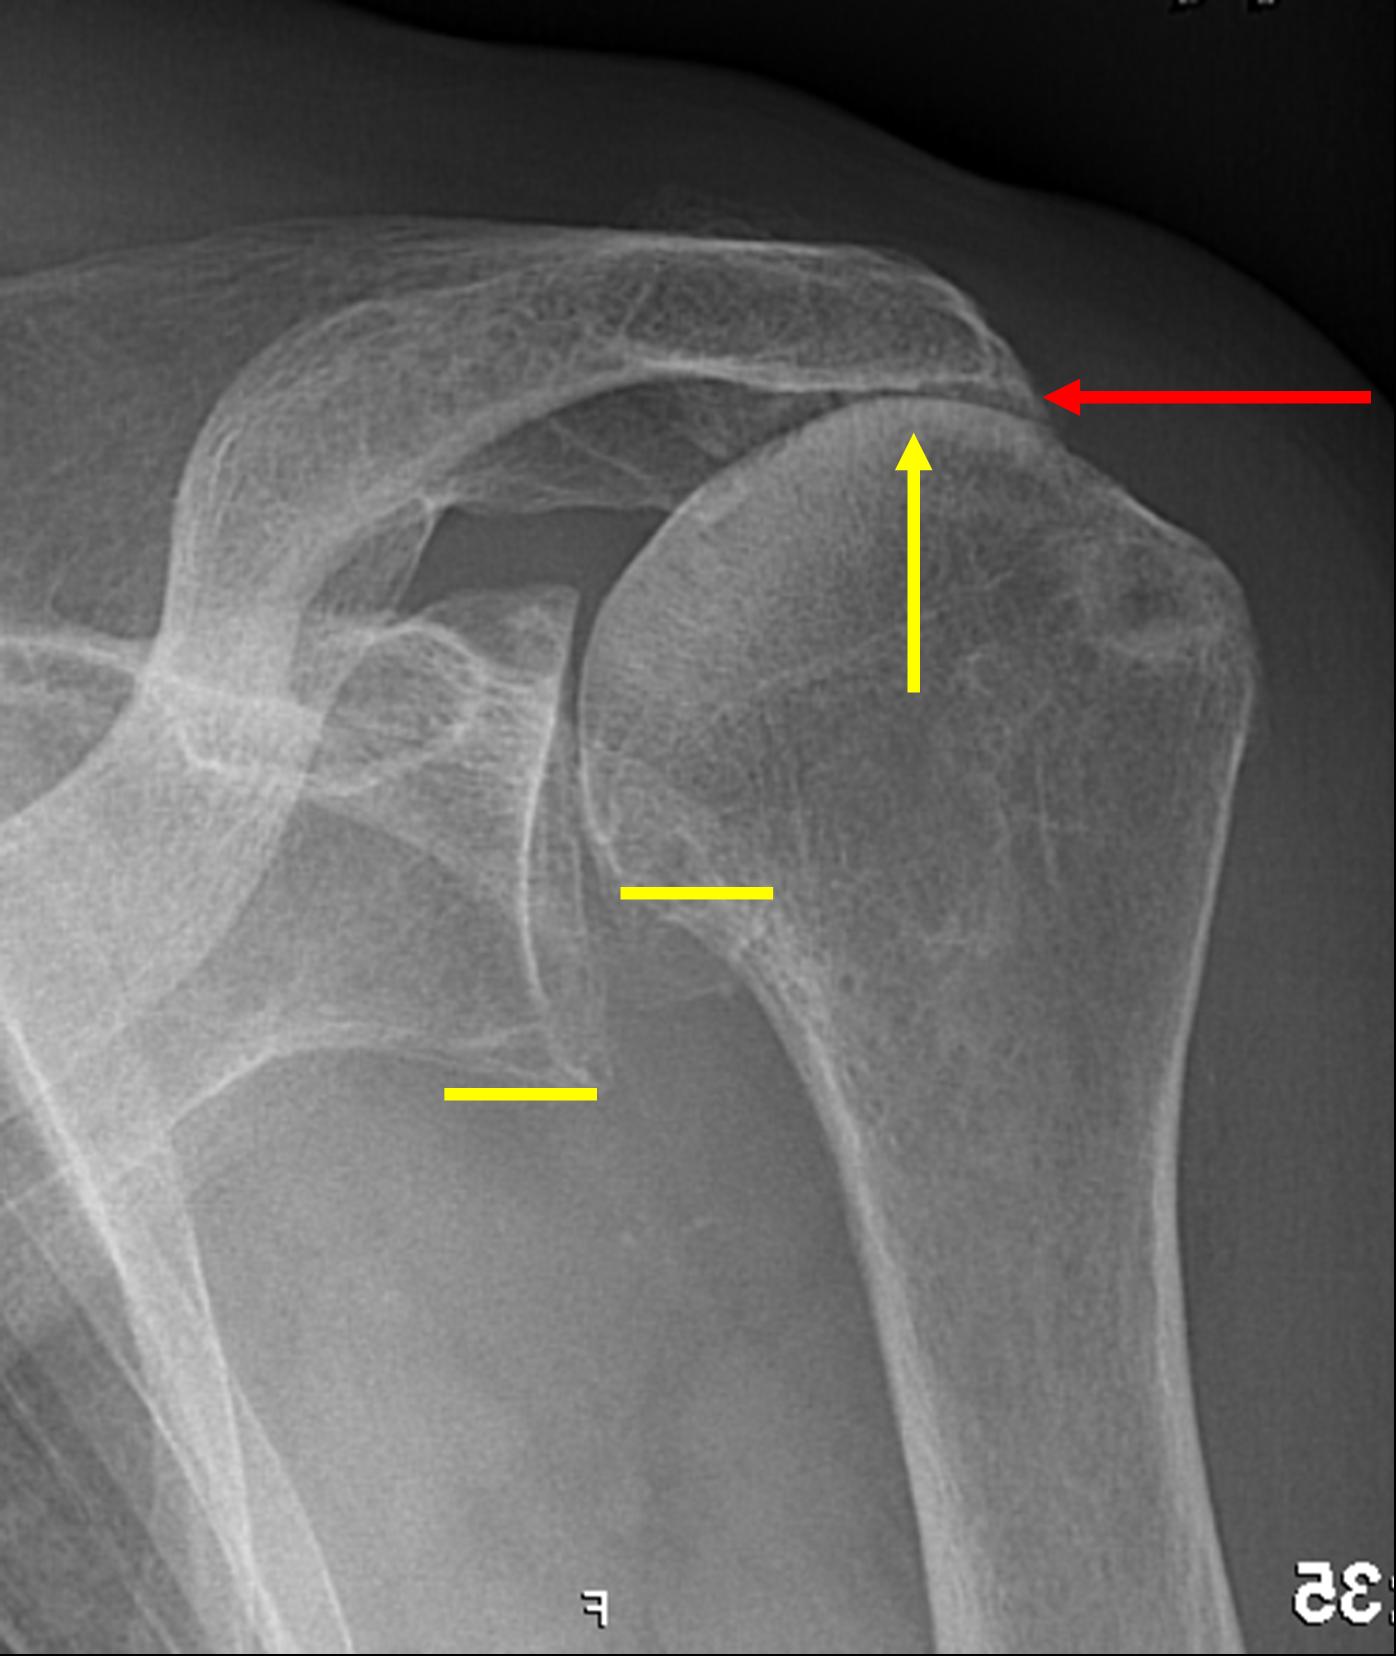

I diagnose rotator cuff tears based on history, physical exam and plain x-rays. Often I also resort to additional imaging studies such as a shoulder arthrogram or MRI. It should always be done in that order. In the shoulder exam I am ... Read Document